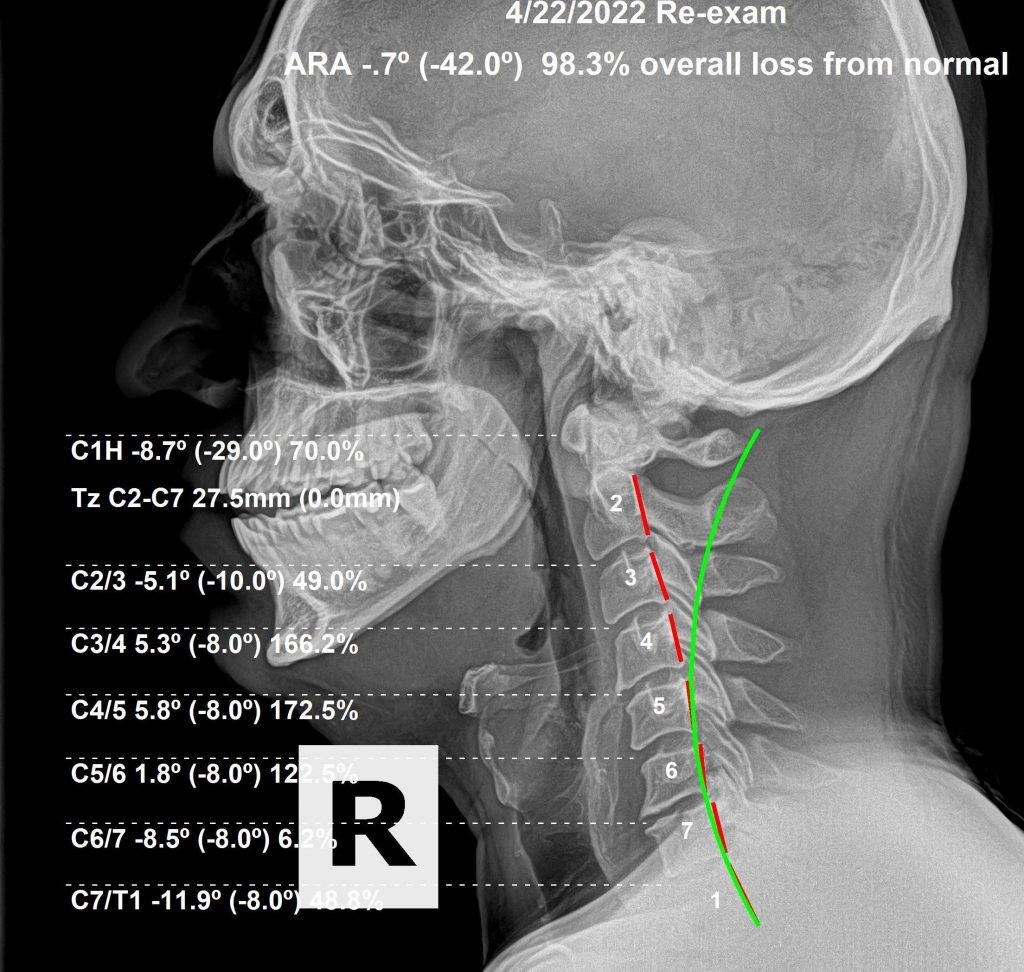

This is a 39-year-old male who sought care for low back problems. His lumbar dysfunction was so severe, he couldn't work out, could barely drive due to pain, and was beginning to lose quality of life.

As we routinely do, we X-rayed his spine. We found greater evidence of spondylosis and degeneration in his neck than in his low back — meaning the non-symptomatic alignment problems in his neck had been present far longer than the symptomatic presentation in his low back. We recommended a care plan and proceeded to adjust when necessary, where necessary, to correct subluxations and ensure strong brain–body connections.

The results of his first round of care were outstanding. He returned to his level of exercise, and his overall quality of life improved significantly. We corrected his curvature from a +1 degree curve (102% loss of normal curve) to a -8.8 degree curve (a 70% loss) — an almost 30% improvement. Normal is -42 degrees.

When he returned almost a year later, his curve had begun to worsen. He had lost 8.1 degrees of curvature — and his symptoms had begun to return as well. The third X-ray tells the story of what happens without maintenance.